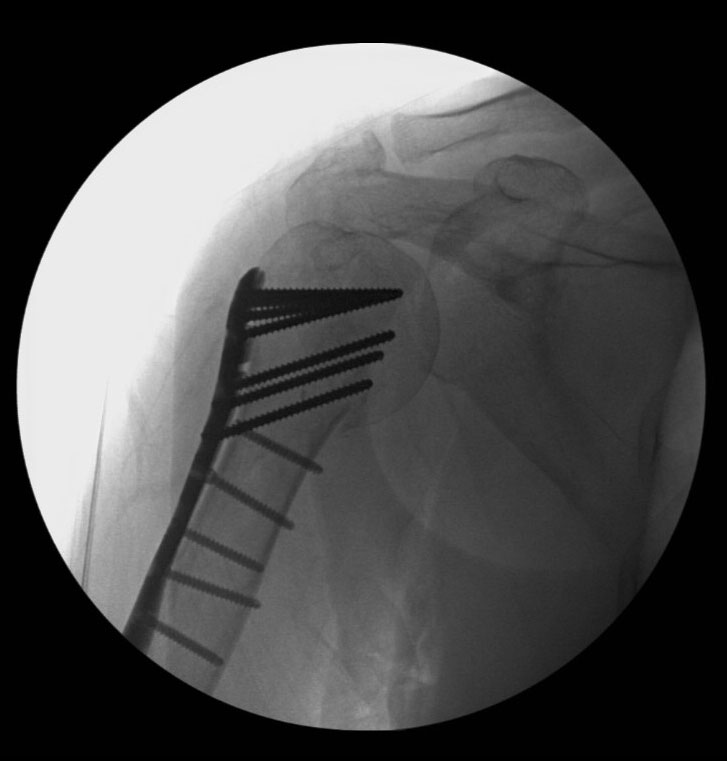

On these views it was clear that the fracture was extensive, and that surgery provided the best chance for the patient to return to full and pain-free activity. The operation for this fracture involves a plate and screws, which hold the fracture in together and allow quick healing in the correct position. After carefully reducing the fracture (returning the frragments of bone to their appropriate place), the plate is secured along the bone and the screws are placed.

An X-ray is taken during the operation to confirm the position of the bone and hardware, and in this case shows that the anatomy of the bone has been restored.

X-ray taken during the operation confirms the anatomy of the bone has been restored.